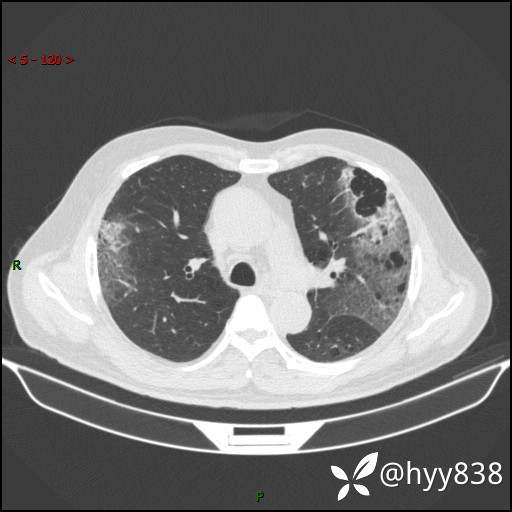

一周前胸部CT